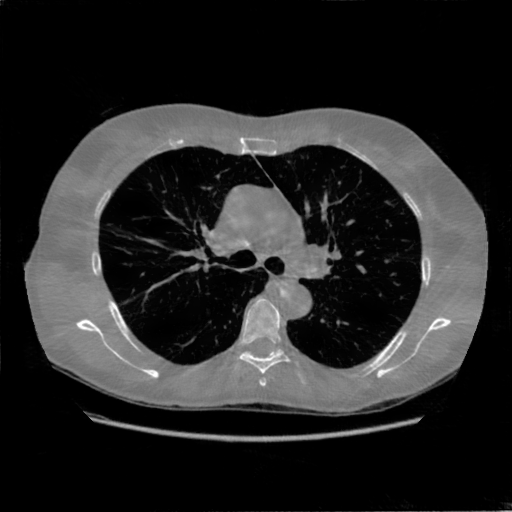

4.4 Limited-Angle CT Reconstruction

To test the proposed framework’s performance on limited-angle reconstruction, we redo the experiment in the above section with the angular range changing from to for parallel-beam geometry and to for fan-beam geometry, one projection per degree. The experiment results are shown in Fig.6. Also, the ground truth and the limited-angle CT reconstruction results of different methods are shown in the row of Fig.7 (parallel-beam, LIDC-IDRI dataset), and Fig.8 (fan-beam, LIDC-IDRI dataset).

(a) Ground Truth

30.15dB

(b) ASD-POCS

39.35dB

(c) RBP-DIP

27.10dB

(d) DIP

23.88dB

(e) MED50

20.59dB

(f) RED-CNN